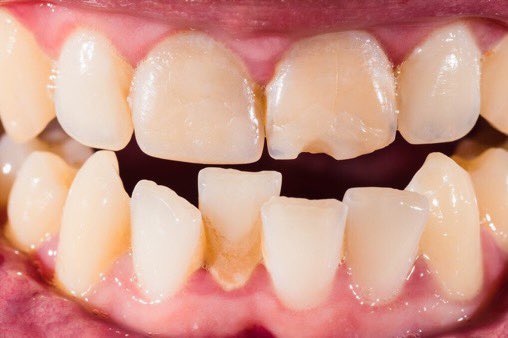

اللثة السليمة:

لمعرفة اللثة المريضة يجب أولا معرفة السليمة ونعرف الاختلافات البسيطة بين جميع الأعراق.اللثة السليمة لونها زهري (غالبا)ملتصقة بالأسنان لامعة(غالبا)لا تنزف عند اللمس أوالتفريش أو بدون سبب/بعض البشرلديهم تصبغات سمراء طبيعية #صحة_أسنانك